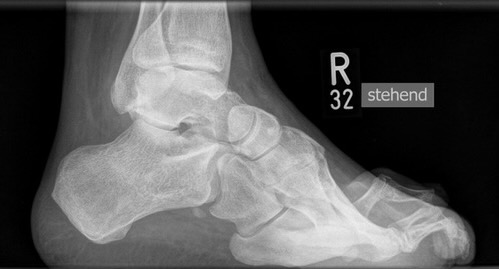

• Fuß belastet dp und seitlich (Abb. 14 und 15)

Typische Merkmale der Standard-Seitaufnahme des Fußes im Stand

• Knöchelgabel ist außen rotiert

• Talus und Calcaneus verlaufen fast parallel

• Sinus tarsi ist einsehbar

• Subtalare Gelenklinie verläuft horizontal und ist breit einsehbar

• Der Abstand Malleolus medialis zum Os naviculare ist verkürzt

• Der Calcaneus erscheint verkürzt

• Der Krümmungsscheitel des Fußes ist erhöht

• Calcaneus pitch ist meist erhöht, der Rückfuß Equinus ist eher selten 12